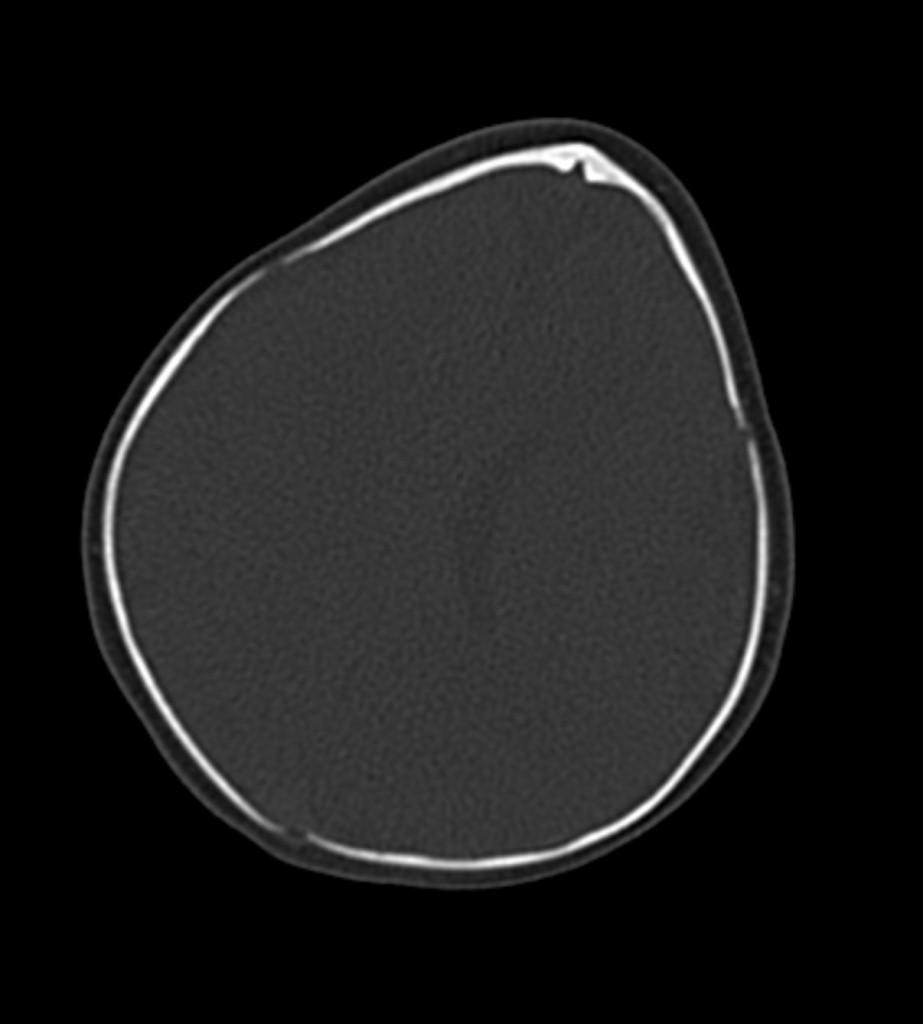

CT images of the brain revealed the triangular appearance of the frontal skull.

Trigonocephaly refers to the triangular appearance of the frontal skull created by premature fusion of the metopic suture (metopic craniosynostosis).